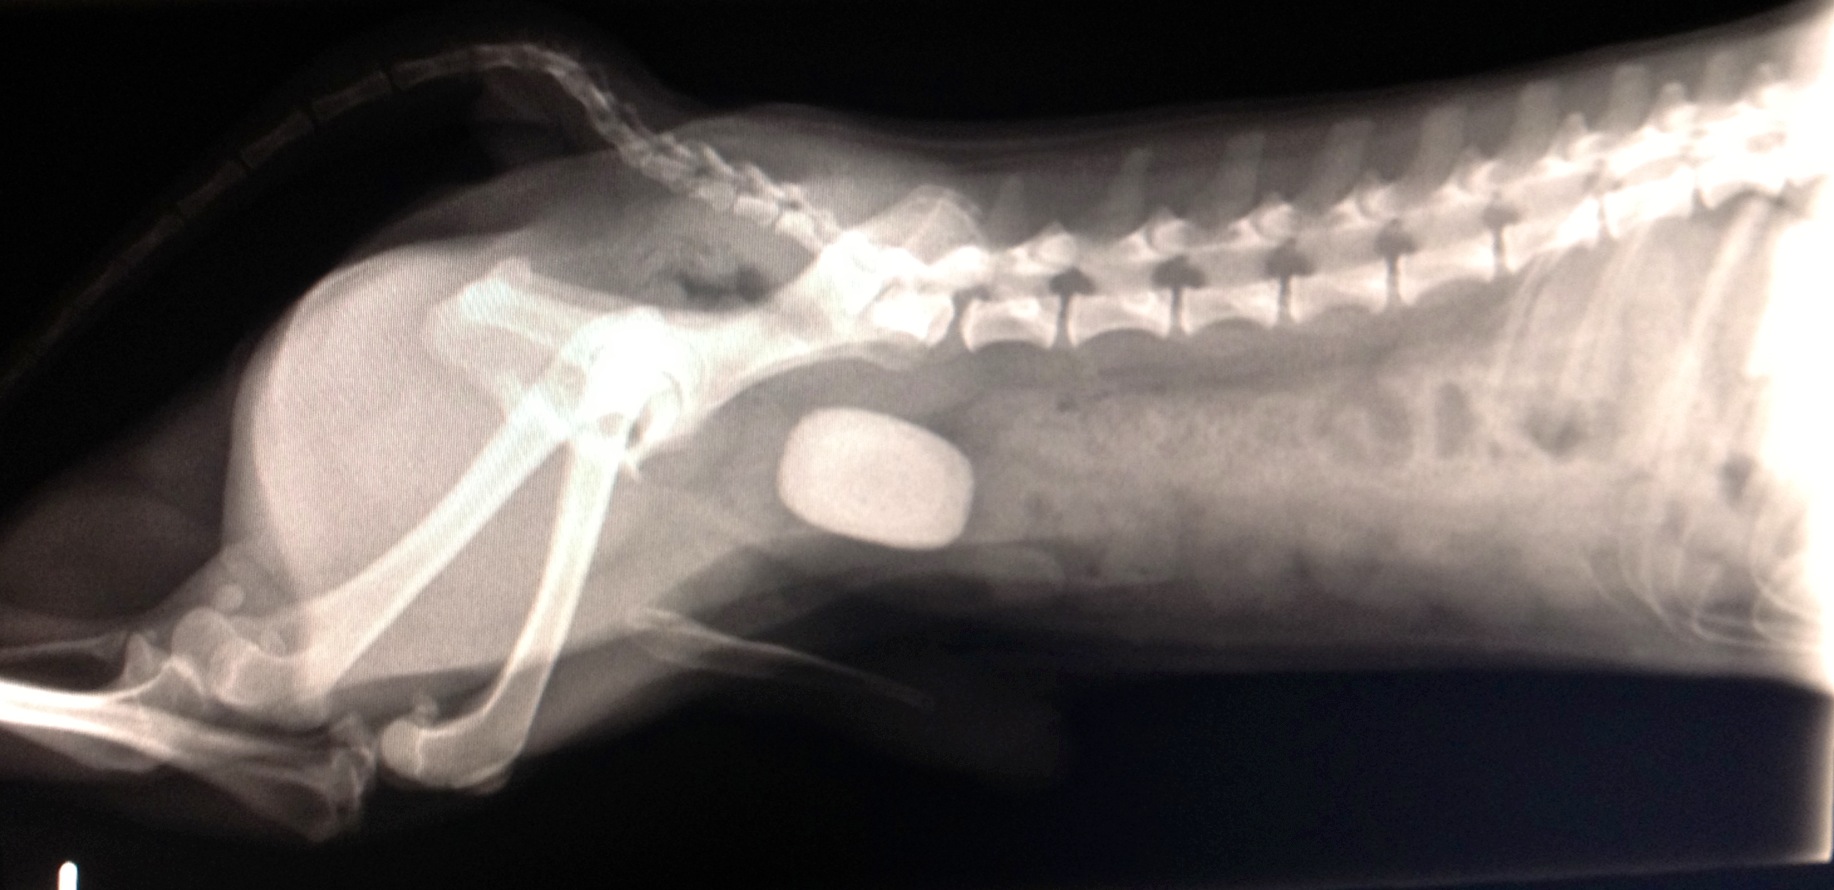

Prince is one of the kindest souls we have encountered; Prince was confiscated by animal control officers due to the severe stage of neglect he was in, in addition of being emaciated he was also in immediate need of splenectomy surgery, in order to remove his oversize spleen which was almost to the point of bursting. Thanks to the help of Dr. John Clark of the Community Veterinary Clinic of Vero, Prince has a brand new quality of life.